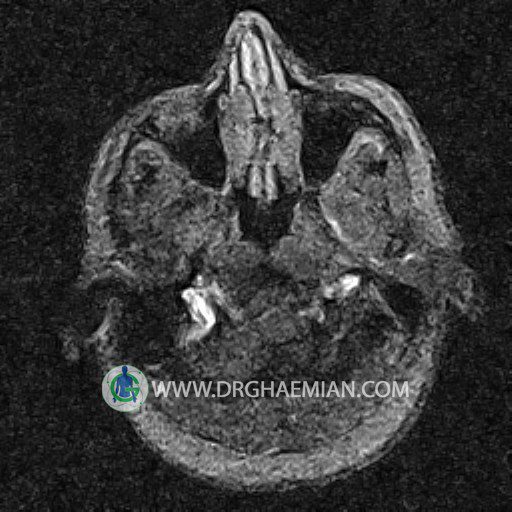

ام آر وی یک روش تصویربرداری دقیق و غیر تهاجمی است که برای معاینه ورید های بدن و ارزیابی سلامت رگ ها استفاده می شود. ورید ها خون را از اعضای بدن به قلب باز می گرداند تا دوباره اکسیژن و مواد مغذی به خون داده شود. ام آر وی جریان خون را ارزیابی و موارد غیرعادی مضر مانند لخته های خونی را شناسایی می کند. در این کیس ترومبوز دیواری مغز در سینوس عرضی راست و ترمبوز جزئی در سینوس عرضی چپ دیده می شود.

(With & Without contrast)

Technique: TOF ( time of flight ).

– Narrowing of left transverse sinus with filling defect & inthimal irregularity

suggestive for partial thrombosis

– Inthimal irregularity in anterior wall of right transverse sinus suggestive for mural thrombosis

are seen